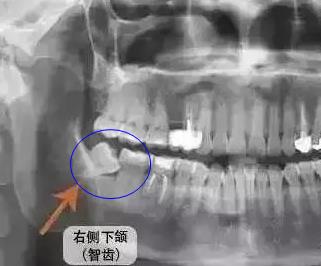

1、右側(ce) 下頜智齒傾(qing) 斜,已經開始抵住前麵一顆磨牙,這種需要拔除,否則會(hui) 造成食物殘渣堆積,齲壞或者是擠到鄰牙。